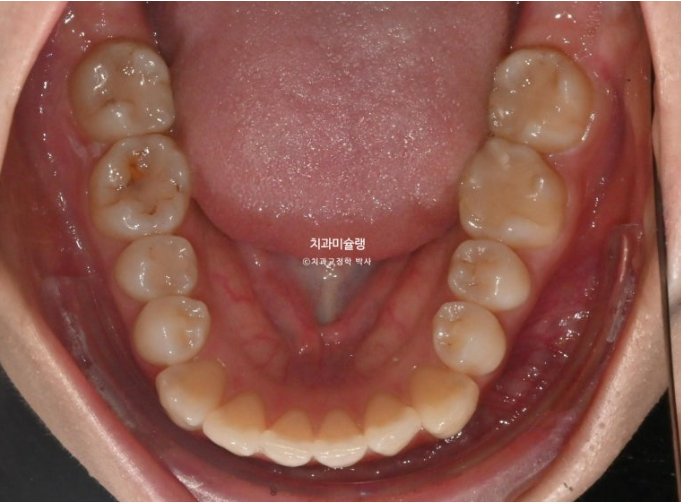

25.03

중심선 불일치, 덧니, 반대교합 등이 보입니다.

절단교합도 보이고

앞니쪽은 뒤죽박죽이나 그에 비하면 어금니 교합은 아름다운 1급 교합관계를 보입니다.